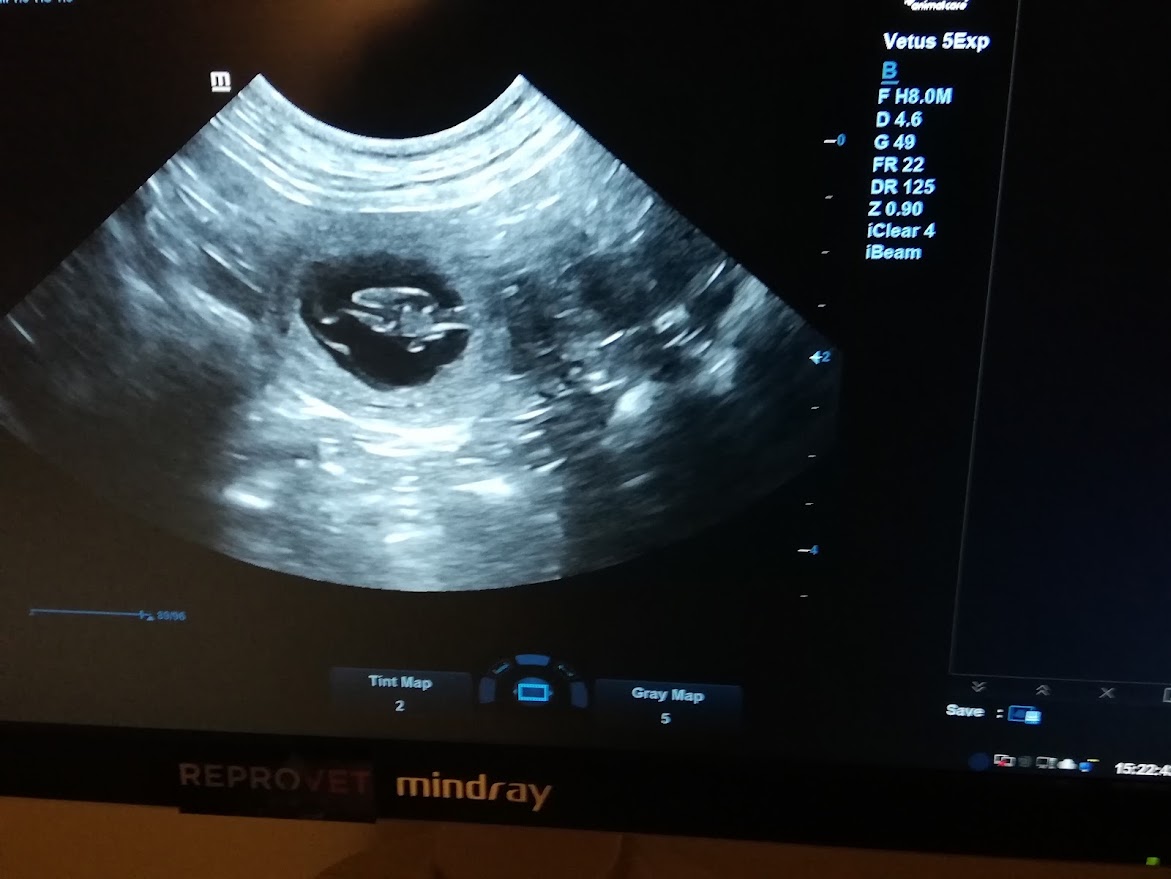

Pipsan ulträäni 25.1.2024

Kävimme tänään ultraamassa Pipsan ja pentuja näkyi tulevan! Toivotaan että kaikki ne säilyvät synnytykseen asti. Pipsalla ollut hieman raskausapahointvointia viime päivinä. Kohta pitäisi ruokahalun kasvaa.